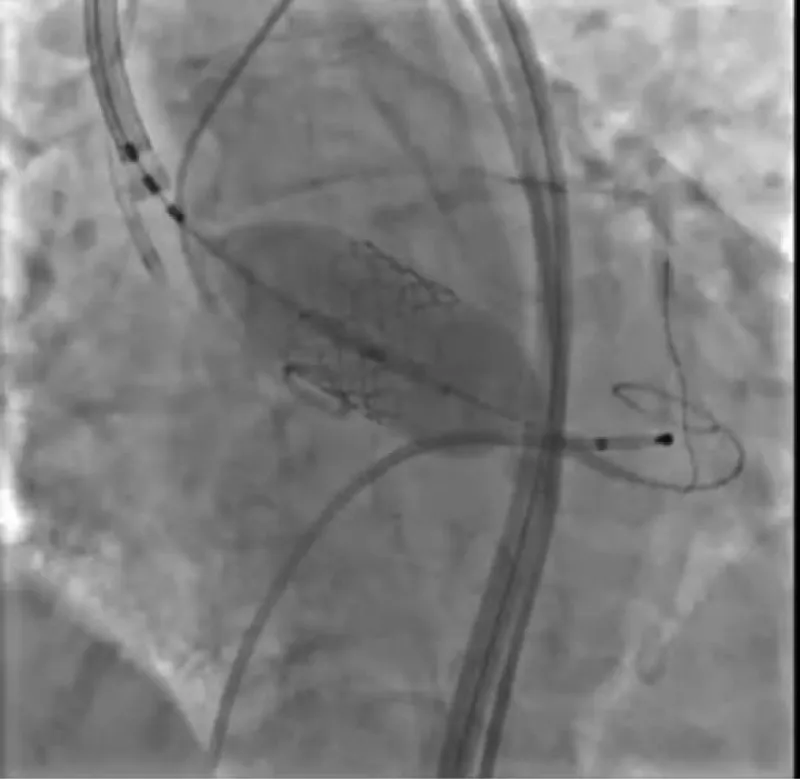

With the support of deep sedation, an angio-guided right femoral access was obtained, and a 12F introducer was advanced. We crossed the aortic valve with an Amplatzer left 1 catheter with a 0.035” wire and exchanged the wire with an extra-stiff Safari. We performed aortic Valvuloplasty with a Nucleus balloon 18 x 40 mm. (Figure 7) Then, we exchanged the wire and advanced an IMPELLA CP device, starting a protected PCI on LM. (Figure 8) An EBU 4.0 catheter was advanced, the stenosis was crossed on the Left Main (LM) and mid-Left Anterior Descending artery (LAD) using a BMW guide wire, and with the aid of a microcatheter a 0.014” Rotawire was positioned, followed by rotational atherectomy using a 1.5 mm burr on LM and mid LAD, (Figure 9) and a 2.0 mm burr on LM alone (Figure 10). This was followed by predilation with a 2.5 x 20 mm SC balloon and the implantation of a 2.5 x 32 mm Synergy drug-eluting stent (Figure 11). Then, the Left Main was predilated with a 3.5 x 12 mm NC balloon, and a 4.0 x 15 mm Xience Sierra drug-eluting stent was implanted and post-dilated with a 4.5 x 8 mm SC balloon (Figure 12). Immediate angiographic control confirmed a successful result. Then we removed the IMPELLA CP device and advanced a 14F e-sheath Edwards on the right femoral artery, crossed the aortic valve with a Safari extra-stiff wire, and performed a Sapien 3 23 mm valve implantation with a good angiographic result (Figure 13). Post-procedural echocardiographic and angiographic assessment confirmed the valve was correctly positioned, with no significant gradient and a minimal residual leak. The procedure was uneventful, and the patient was discharged on the fourth day with triple therapy: Aspirin 100 mg once daily, Clopidogrel 75 mg once daily, and Apixaban 2.5 mg twice daily. At the quarterly follow-up, the patient reported hospitalization for anemia, requiring a transfusion of 3 units of packed red blood cells. Endoscopic exams were negative, and hypochromic, normocytic anemia persisted. Given the patient’s CHA2D2-VASc score of 5, HAS-BLED score of 4, and recent dual Drug-Eluting Stent (DES) implantation, she was admitted for left atrial appendage percutaneous closure. Before this procedure, a repeat coronary angiography showed good results in the previously implanted stents (Figure 14). Subsequently, through a right femoral percutaneous approach using a 12F introducer, a 22 mm Amulet device was positioned for left atrial appendage closure (Figure 15). The procedure was completed without complications. At the 4-year follow-up, the patient presented in good hemodynamic status, with an echocardiographic ejection fraction of 55%. She continued on clopidogrel 75 mg once daily therapy.

Download Image

Figure 11: PTCA on LAD.

Figure 12: PTCA on LM.

Figure 13: Sapien 3 23 mm.